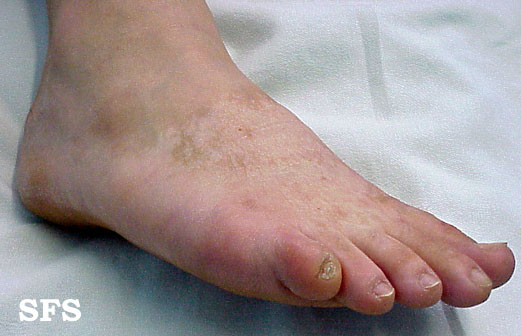

naevus achromic